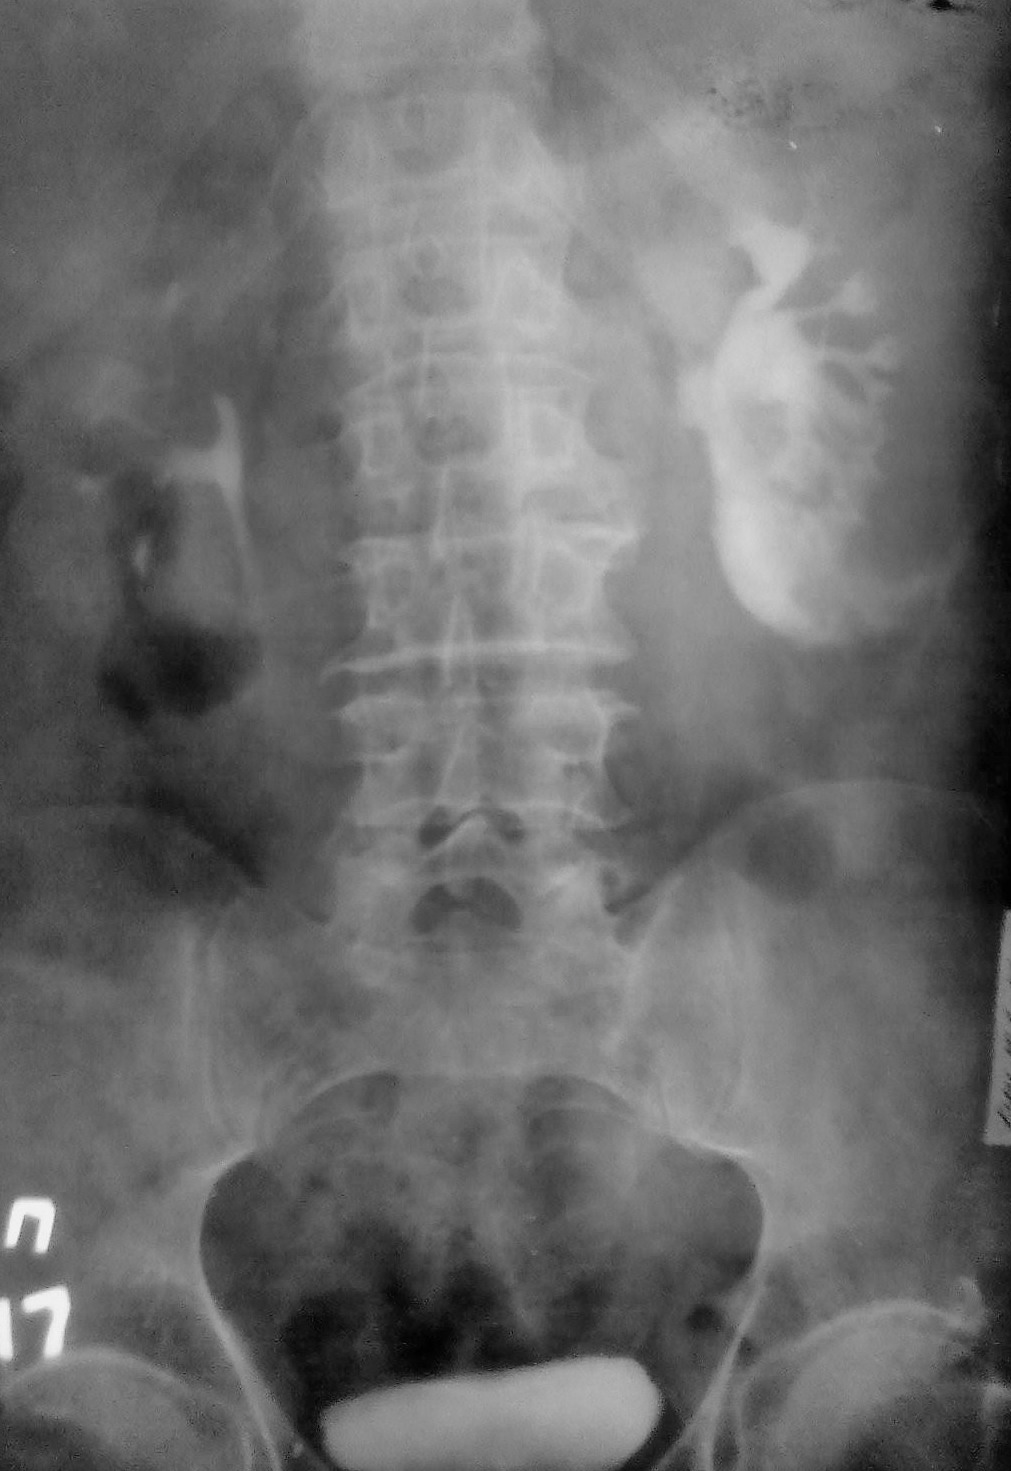

Представляю Вам в\в урографию без коментариев. Случай классический.

Разрыв почки? Затек контраста?

Все правильно, это тоже криминальная травма, сукапсулярный и капсулярный разрыв нижнего полюса левой почки и затек контраста паранефрально...

Спасибо за "рихтовку" снимков, просто хотелось показать как выглядит затек в паренхиму, под капсулу и вне капсулы...в этом плане случай очень показателен. Кстати, больного не оперировали, заживление, он жив и, как видите, судится с обидчиками....